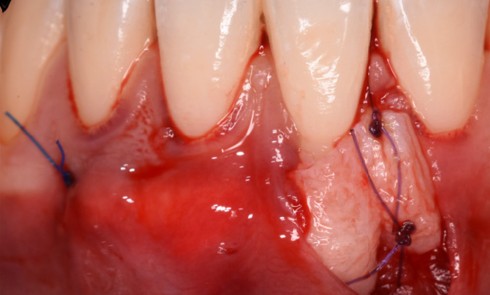

La déchirure cémentaire constitue-t-elle un problème minoré ?

Les déchirures cémentaires correspondent à un détachement partiel ou complet du cément. Leur prévalence est estimée entre 2 et 5...Rayons X — Réalisation d’une radiographie panoramique